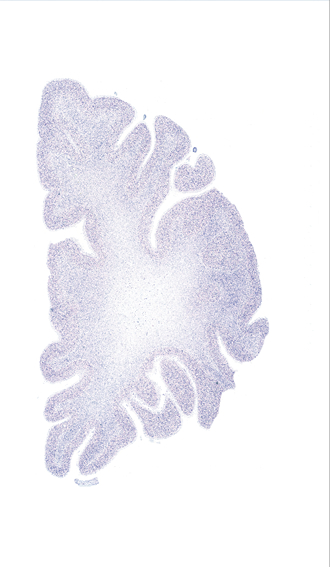

Frontal sections (Nissl) from the Atlas Brain: Gallery Slice Single

-31,2 mm

Slice ID: r2-1053

Plate NR: 06

Position: -31,2 mm